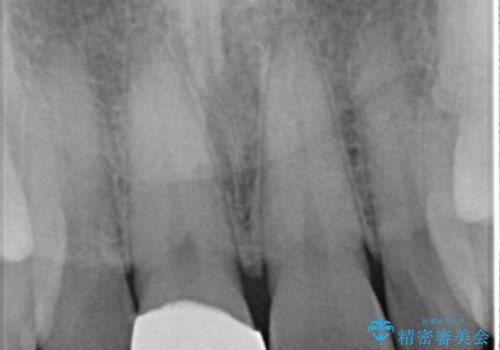

- 上の前歯の一部が欠けてしまったので治療を希望し来院された患者様です。

破折状態から歯髄(歯の神経)は保存できると判断し、クラウンでの治療を計画しました。

前歯が綺麗になったと大変満足して頂けました。